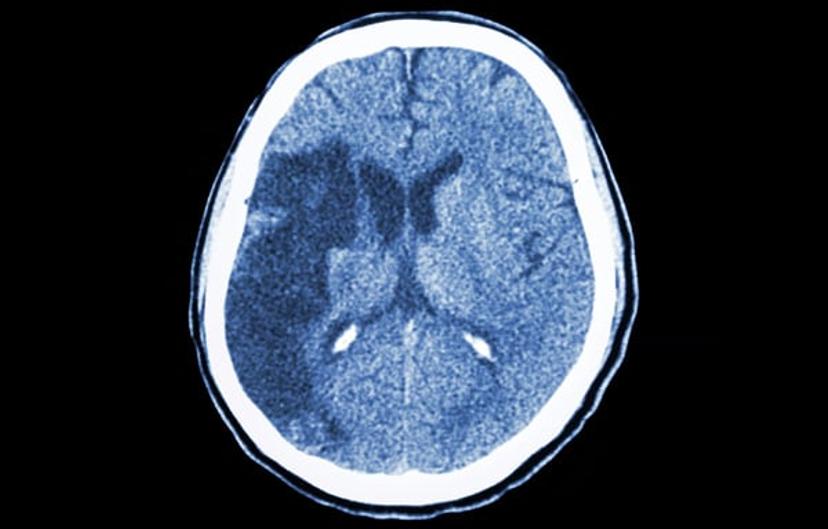

Ischemic stroke is caused when blood supply to the brain is cut off, most often as a consequence of atherosclerosis with the formation of blood clots. Rapid treatment is necessary to prevent damage to the brain through restoration of oxygen supply. Factors in damage caused by ischemic stroke, including exitotoxicity and oxidative stress, have been identified as potential targets for new theraputics.

We work with fragment-based drug discovery with a focus on protein-protein interactions in the brain. Our aim is to make high-quality small-molecule inhibitors that can be used in pharmacological studies and potentially serve as leads for drug development. The proteins we work with are involved in excitotoxicity and oxidative stress. One of the diseases this is relevant for is ischemic stroke, where there is only one drug-type on the market — recombinant tissue plasminogen activators (rtPAs), which break up the blood clot. Still, ischemic stroke is the third leading cause of death worldwide and a leading cause of adult disability. With our work, we hope to identify new therapeutic principles against ischemic stroke. Our protein targets are also involved in other diseases and conditions such as inflammation, inside as well as outside the brain.